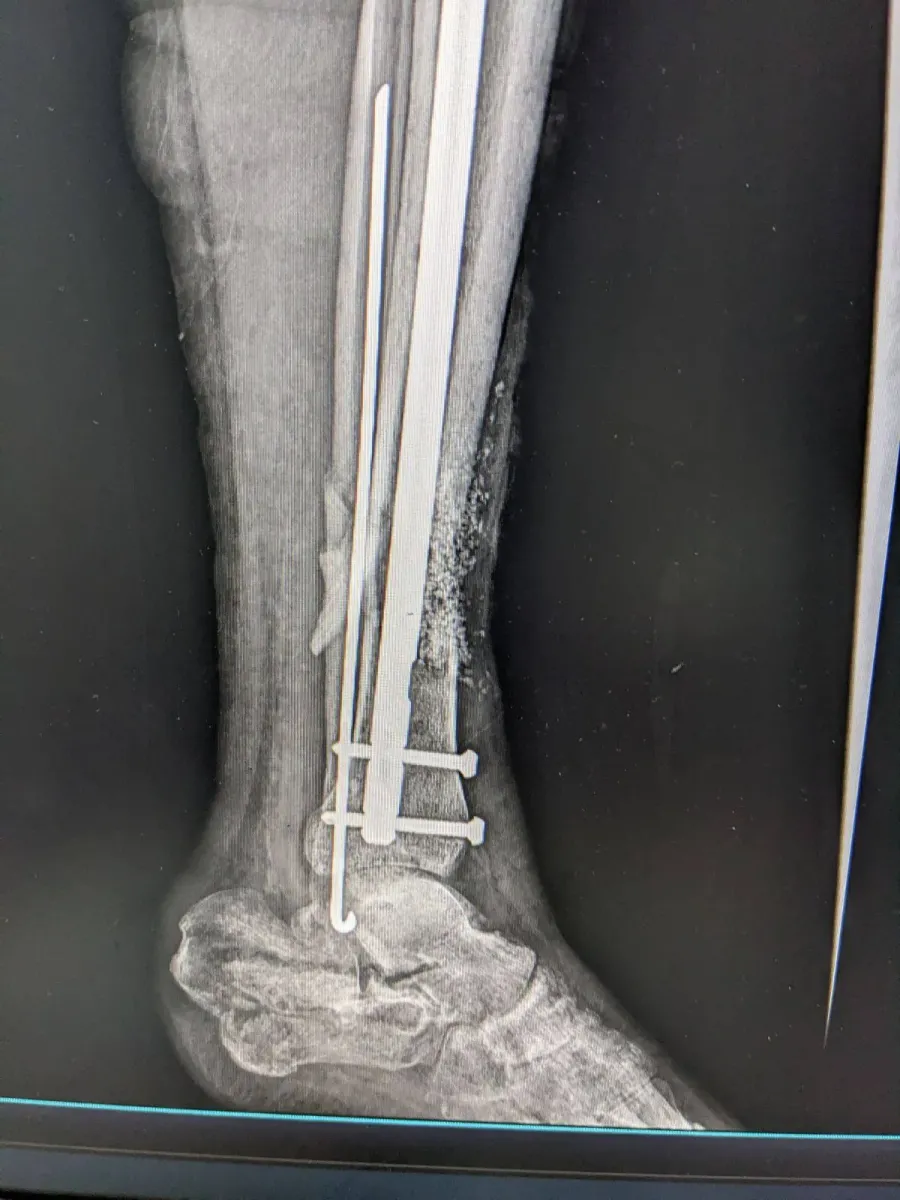

У закладі проведено реконструктивне оперативне втручання військовослужбовцю з післятравматичним дефектом кісткової тканини, повідомляє КНП "Богородчанська центральна лікарня" Богородчанської селищної ради.

Під час операції лікарями було виконано відновлення цілісності кістки із застосуванням аутокісткової пластики (власна кістка пацієнта) у поєднанні з біоактивним біосклом, що дозволяє:

- стимулювати регенерацію кісткової тканини;

- покращити остеоінтеграцію;

- зменшити ризик ускладнень;

- сприяти швидшому функціональному відновленню.

Використане біоскло було придбане за кошти лікарні, що дало можливість забезпечити пацієнта сучасними матеріалами без додаткового фінансового навантаження.

Втручання проведено командою травматологів-ортопедів із дотриманням сучасних принципів реконструктивної хірургії.